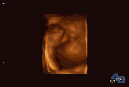

对于很多孕妈妈来说,做超声影像(四维彩超)已成常规产检流程,在孕期检查时它能及时发现并预防疾病,保障孕妇健康和胎儿正常发育。相比于普通B超抽象的黑白图像,橘色的超声影像(四维彩超)让准爸妈们第一次看清了孩子的“模样”。

一般做产检的时候会做B超、三维彩超、超声影像(四维彩超)。彩超其实还是黑白的,而三维、超声影像(四维彩超)做出来才是橘色的,也并非彩超就是彩色的。

超声影像(四维彩超)不仅仅是感觉胎宝宝的呼吸和运动,还能亲眼目睹他们的一举一动和乖巧的秀容。更为重要的是,超声影像(四维彩超)能够多方位、多角度地观察宫内胎儿的生长发育情况,为早期诊断胎儿先天性体表畸形和先天性心脏疾病提供准确的科学依据。在百佳,我们还为来做超声影像(四维彩超)的孕妈妈,准备了记录宝宝这珍贵的画面。